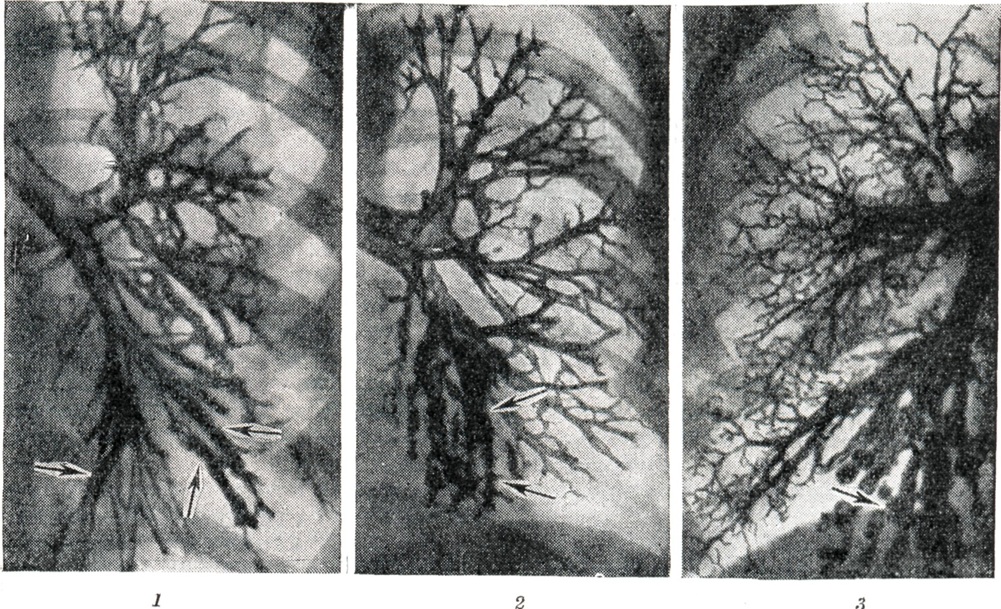

При бронхографии и бронхокинематографии устанавливают расстройство функциональной деятельности бронхиального дерева — неравномерное (ускоренное или замедленное) заполнение и опорожнение бронхов, бронхоспазм, бронходилатацию. В области Б. калибр бронхов почти не меняется при дыхании (рисунок 3). Контрастное вещество длительно задерживается в Б., особенно в мешотчатых, и не поступает в более мелкие бронхиальные разветвления.